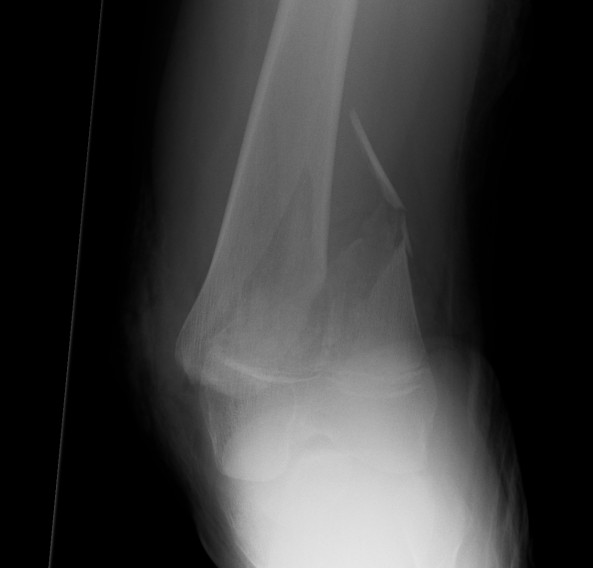

Salter Harris I

Salter Harris II

Displaced

MUA +/- ORIF